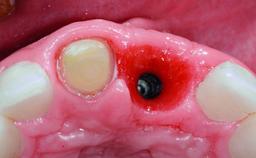

A 32-year-old female Caucasian patient with a compromised maxillary right central incisor was referred to us by a general dentist. Her chief complaints were discomfort and mobility of tooth 11 with unsatisfactory esthetics due to discoloration. The patient reported a previous trauma, some years earlier, as the origin of pathology on the afflicted tooth. Anamnesis was negative for any other dental or periodontal pathology in the remaining dentition. The patient did not take any medication and reported to be a light smoker (5–10 cigs/day). She had high esthetic expectations of her treatment. The extraoral examination revealed a high smile line with full exposure of her maxillary teeth and surrounding soft tissue in the area between the second premolars.

Defining Characteristics One missing tooth to be replaced by an implant-borne prosthesis

Placement Protocol Early or late implant placement

Bone Volume Deficient horizontally, requiring prior grafting

Esthetic Risk High